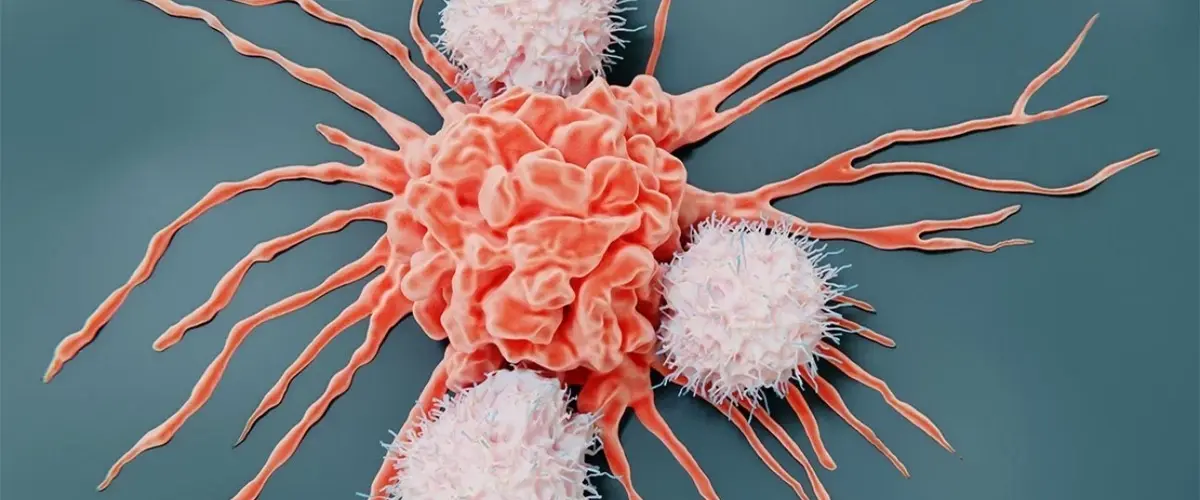

Технологію NK-клітинної терапії розробили вчені з Каліфорнійського університету в Сан-Дієго. NK-клітини, або клітини-кілери, створюють зі стовбурових клітин, а потім модифікують у лабораторії для цілеспрямованої атаки на рак. Як відомо, пухлини зазвичай пригнічують імунні клітини, які намагаються їх атакувати. Це одна з ключових причин, чому деякі методи імунотерапії, такі як CAR T-клітинна терапія, виявилися менш успішними при солідних пухлинах, ніж при раку крові.

У новому підході вчені вирішили відключити рецептор білка TGF-?, який послаблює імунну функцію. Це дало змогу значно посилити протипухлинну активність і подовжити життя гризунам із гепатоцелюлярною карциномою – найпоширенішим типом раку печінки.